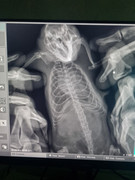

Крысе 8 месяцев. Месяц назад уже лечила ее, так как она хрюкала. Принимала Юнидокс две недели два раза в день. Она выздоровела, но сейчас вновь заболела. Дыхание громкое, часто чихает. Не знаю можно ли ей давать заново Юнидокс или поменять антибиотик. Возможности обратиться к ветеринару нет

Примерный вес крысы 300 гр. Ведет себя активно, хорошо кушает

Нет, тот же антибиотик нельзя снова. Нужен другой. Например ветеринарный  - энроксил. И, всё-таки, ищите возможность сделать рентген. Может, нужно более интенсивное лечение.